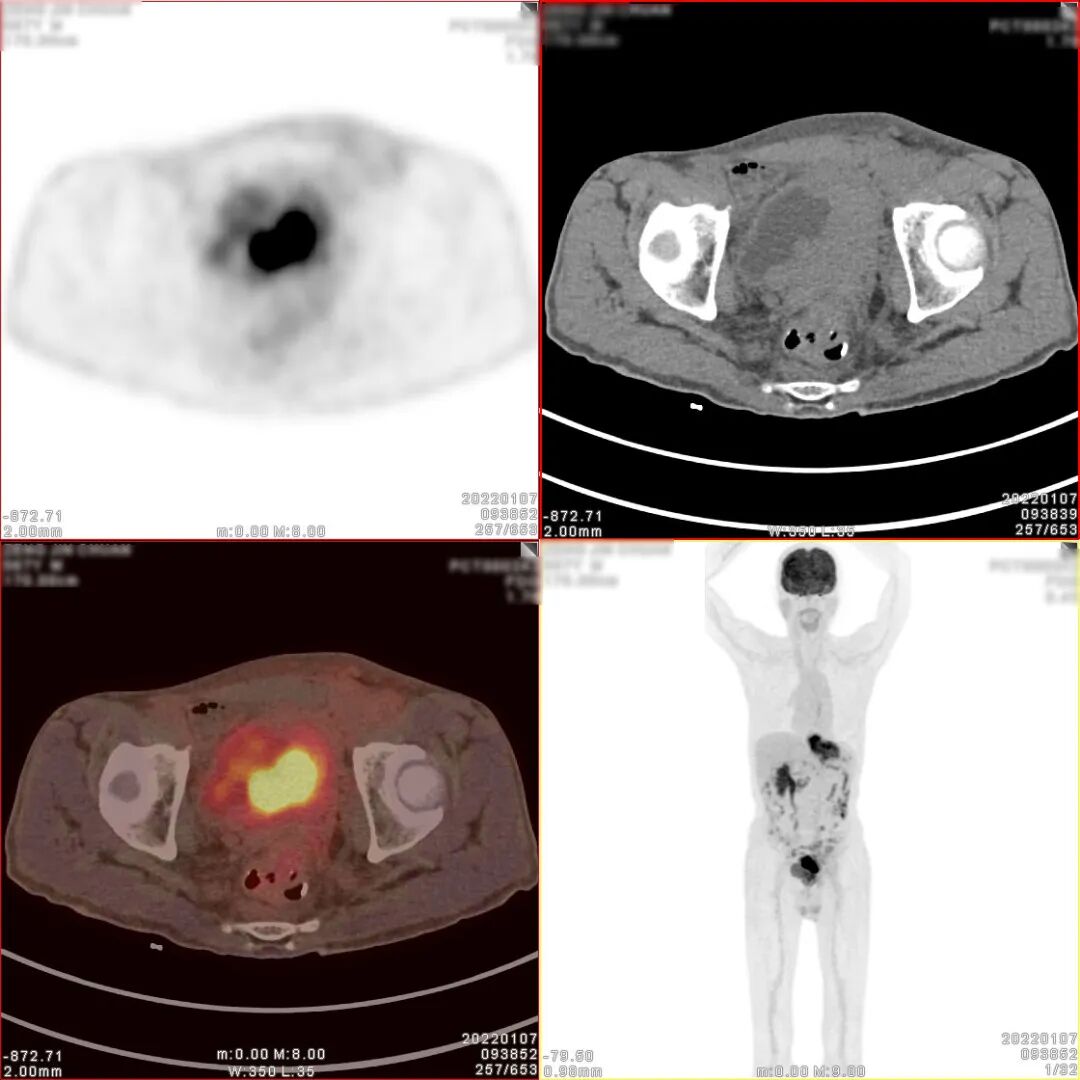

18F-FDG PET/CT检查图像

胃癌术后、化疗后,胃术后缺如,CT 见食管下段与肠道吻合口区软组织明显增 厚,密度较均匀,边缘欠清,PET 于相应部位可见不规则形放射性异常浓聚影,大小 约 71×27×63mm,SUVmax 为 9.5。CT 于左下腹部肠系膜上可见结节状密度增高影, 大小约 14×8mm,密度较均匀,边缘欠清,PET 于相应部位可见结节状放射性异常浓 聚影,SUVmax 为 4.9。CT 见腹盆腔其他部位肠系膜密度稍增高,边缘模糊,PET 于 相应部位未见明显放射性异常浓聚影。CT 见膀胱顶壁、左侧壁、左后壁及膀胱三角 区软组织明显增厚,密度较均匀,边缘欠清,堵塞双侧输尿管下段膀胱入口,并向 下与前列腺分界不清,PET 于增厚的膀胱壁内可见不规则形放射性异常浓聚影,大小约80×34×47mm,SUVmax 为 30.3;CT 见前列腺体积不大,其内可见多个小斑点状 高密度钙化影,PET 于前列腺内可见块状放射性异常浓聚影,大小约 39×36×35mm, SUVmax 为 6.9。CT 于盆腔内右侧髂外血管旁可见稍肿大淋巴结,大小约 10×7mm, PET 于相应部位可见结节状放射性异常浓聚影,SUVmax 为 2.9。

1、胃癌术后、化疗后,食管下段与肠道吻合口区软组织明显增厚,代谢增高, 考虑肿瘤复发病灶;

2、膀胱顶壁、左侧壁、左后壁及膀胱三角区不规则形代谢增高影及前列腺内块 状代谢增高影,考虑膀胱癌并侵犯前列腺;

3、左下腹部肠系膜上结节状密度增高影,代谢增高,考虑转移灶;腹盆腔其他 部位肠系膜密度稍增高,未见代谢增高,请结合临床追踪复查以排外低代谢腹膜 转移灶的可能;

4、盆腔内右侧髂外血管旁稍肿大淋巴结,代谢稍增高,不排外淋巴结转移灶的可能。